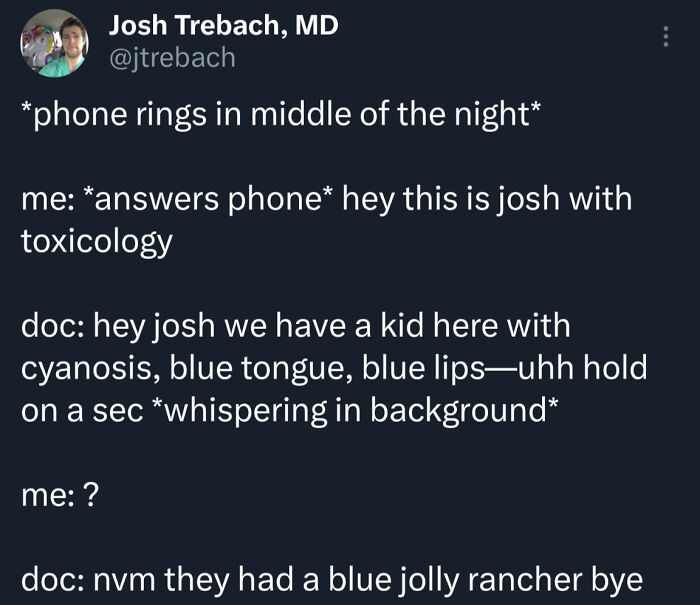

#16 Having To Call Toxicology

Image credits: Felix_B91